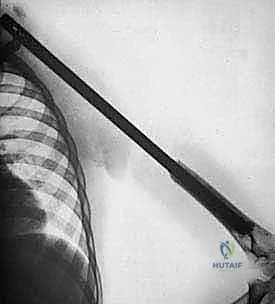

1. التصوير الشعاعي (X-Rays)

الخطوة الأولى والأساسية. تظهر الأشعة السينية تدمير العظم، رد فعل السمحاق (Periosteal reaction)، وتساعد في تحديد طبيعة الورم (هل يبدو حميداً أم خبيثاً؟).

- الكسور المرضية (Pathological Fractures): يضعف الورم بنية العظم السليم. في كثير من الحالات، يكتشف المريض الورم عندما يتعرض لكسر في الكتف نتيجة إصابة تافهة جداً (مثل الاستناد على الذراع أو رفع غرض خفيف).